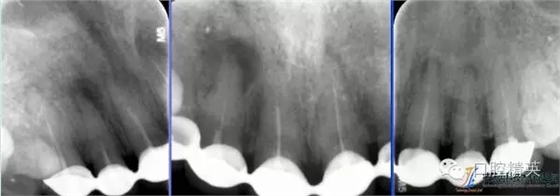

術前根尖片

術后根尖片